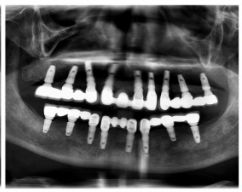

种牙后X光片,戴冠。

通过X光片可以看到,医生虽然尽量设计连冠种植,但还是用了十七个植体,尽管已经是多次调整后的最精简方案,但手术时长依然长达一天。位老先生之前在另一家医院咨询时,医生给的方案是种二十二个植体,光是种植费用就令人大呼“害怕”了。